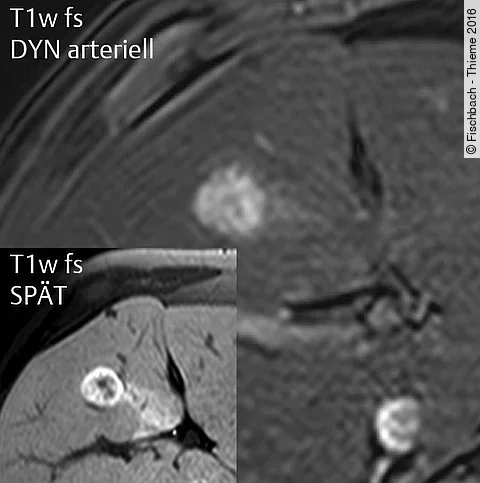

Quiz der Woche31-Jährige mit Raumforderung in der nicht zirrhotischen Leber

Die beschwerdefreie Patientin hatte in der Sonografie eine Raumforderung in der Leber. Dieser Befund bestätigte sich im MRT.